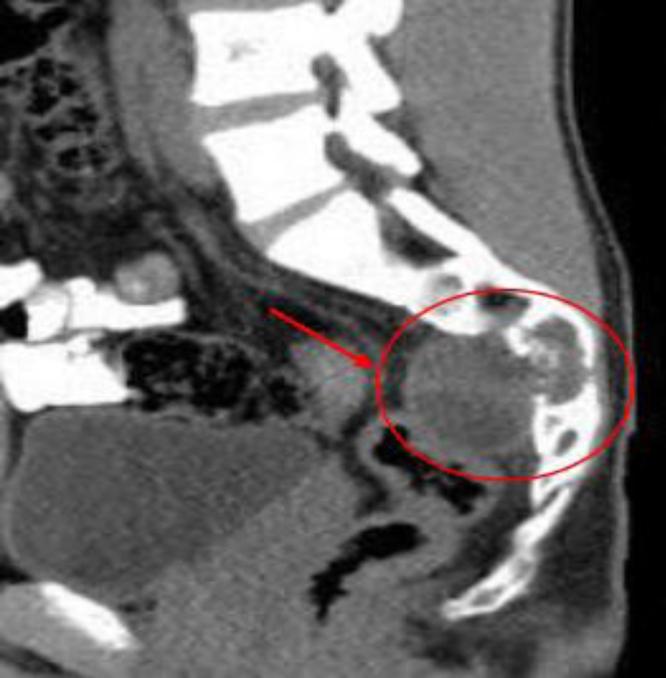

A 17-year-old male with a history of HC disease presented with low back pain radiating to both lower limbs, claudication, and chronic constipation for 5 years. Imaging revealed a large, multiloculated sacral cyst extending retrorectally and presacrally from S3 to S5, involving the spinal canal, compressing the rectum, and causing sacral erosion. A diagnosis of sacral hydatidosis was made, and the patient was started on albendazole, with surgical excision planned.

一名有HC病病史的17岁男性,出现下背部疼痛并放射至双下肢、间歇性跛行及慢性便秘达5年。影像学检查显示一个巨大的、多房性骶骨囊肿,从S3至S5向直肠后方和骶骨前方延伸,累及椎管,压迫直肠,并导致骶骨侵蚀。诊断为骶骨包虫病,患者开始服用阿苯达唑,并计划进行手术切除。